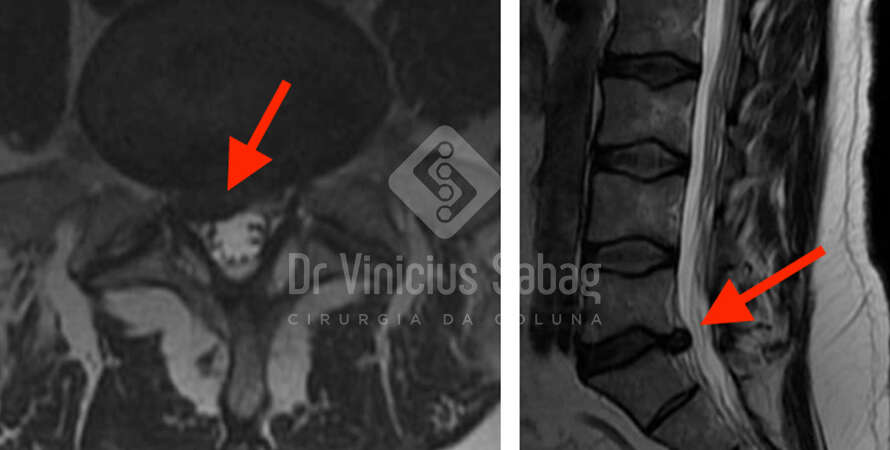

À esquerda: ressonância magnética com hérnia discal lombar volumosa. À direita: cirurgia endoscópica para retirada minimamente invasiva da hérnia.